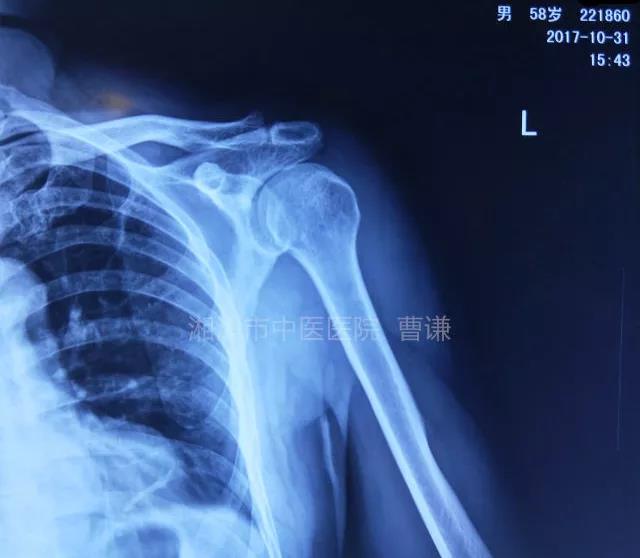

简要病史:骑摩托车跌倒致左肩部肿痛,活动受限,就诊于当地医院,拍片及磁共振检查后诊断为肩袖损伤及肩关节半脱位,予以悬吊固定,因症状缓解不明显就诊于我院。外院拍片情况如下:

应该说是一个典型的“灯泡征”影像,但是并未引起注意。